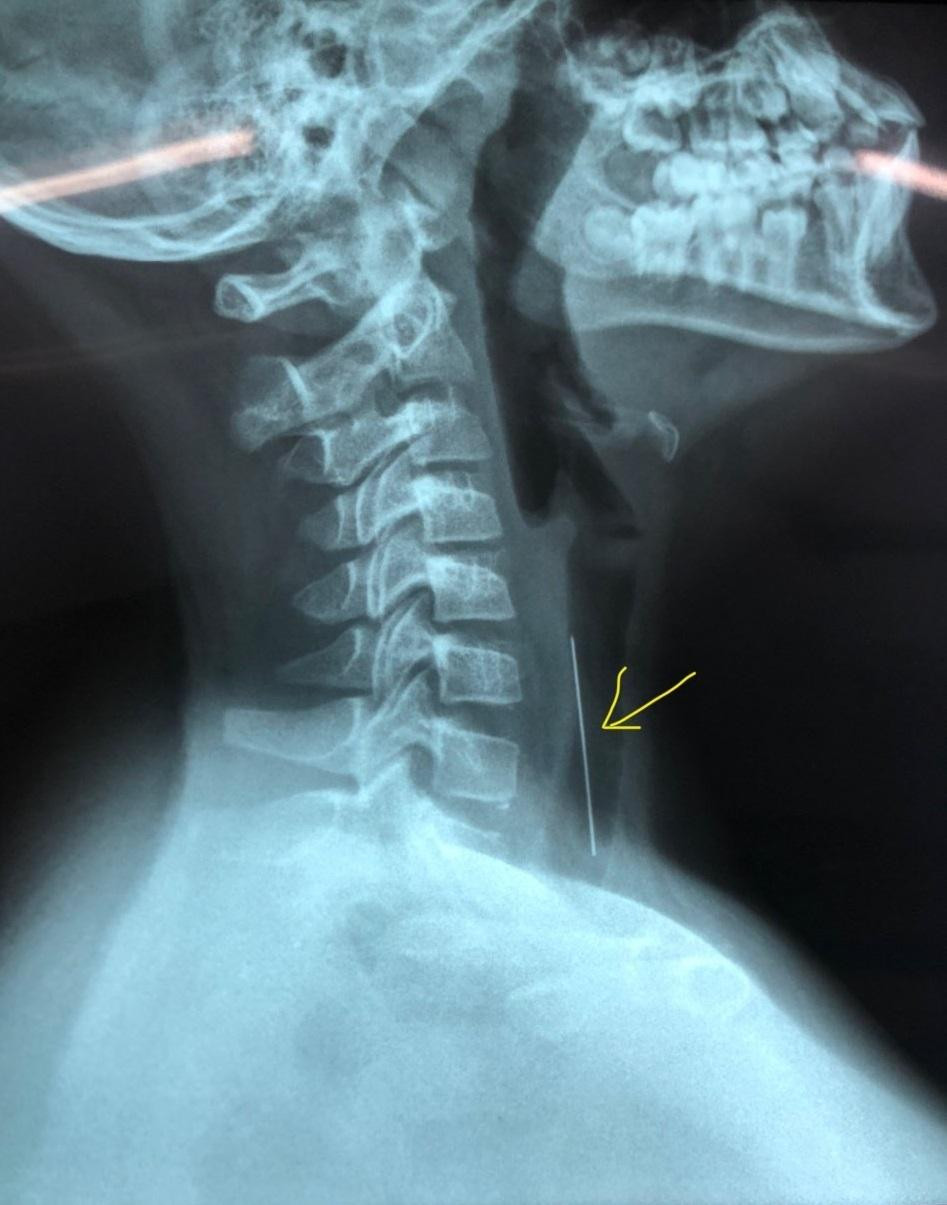

| Hình ảnh kiểm tra cho thấy cây kim dài gần 5cm ghim vào khí quản của bệnh nhi |

Tại Bệnh viện Nhi Đồng 1, kết quả kiểm tra hình ảnh, bác sĩ ghi nhận cây kim, đang nằm trong đường thở của bệnh nhi, đầu nhựa quay xuống dưới, đầu nhọn quay lên trên và ghim sâu vào thành khí quản khoảng 1cm. Sau hội chẩn, các bác sĩ đã quyết định thực hiện nội soi cấp cứu lấy dị vật.

Dị vật được lấy ra ngoài là 1 cây kim dài gần 5cm với 1 đầu nhựa màu cam. Sau nội soi gắp dị vật, sức khỏe bệnh nhi đã bình phục tốt, không còn đau, hết cảm giác khó thở và ăn uống được.